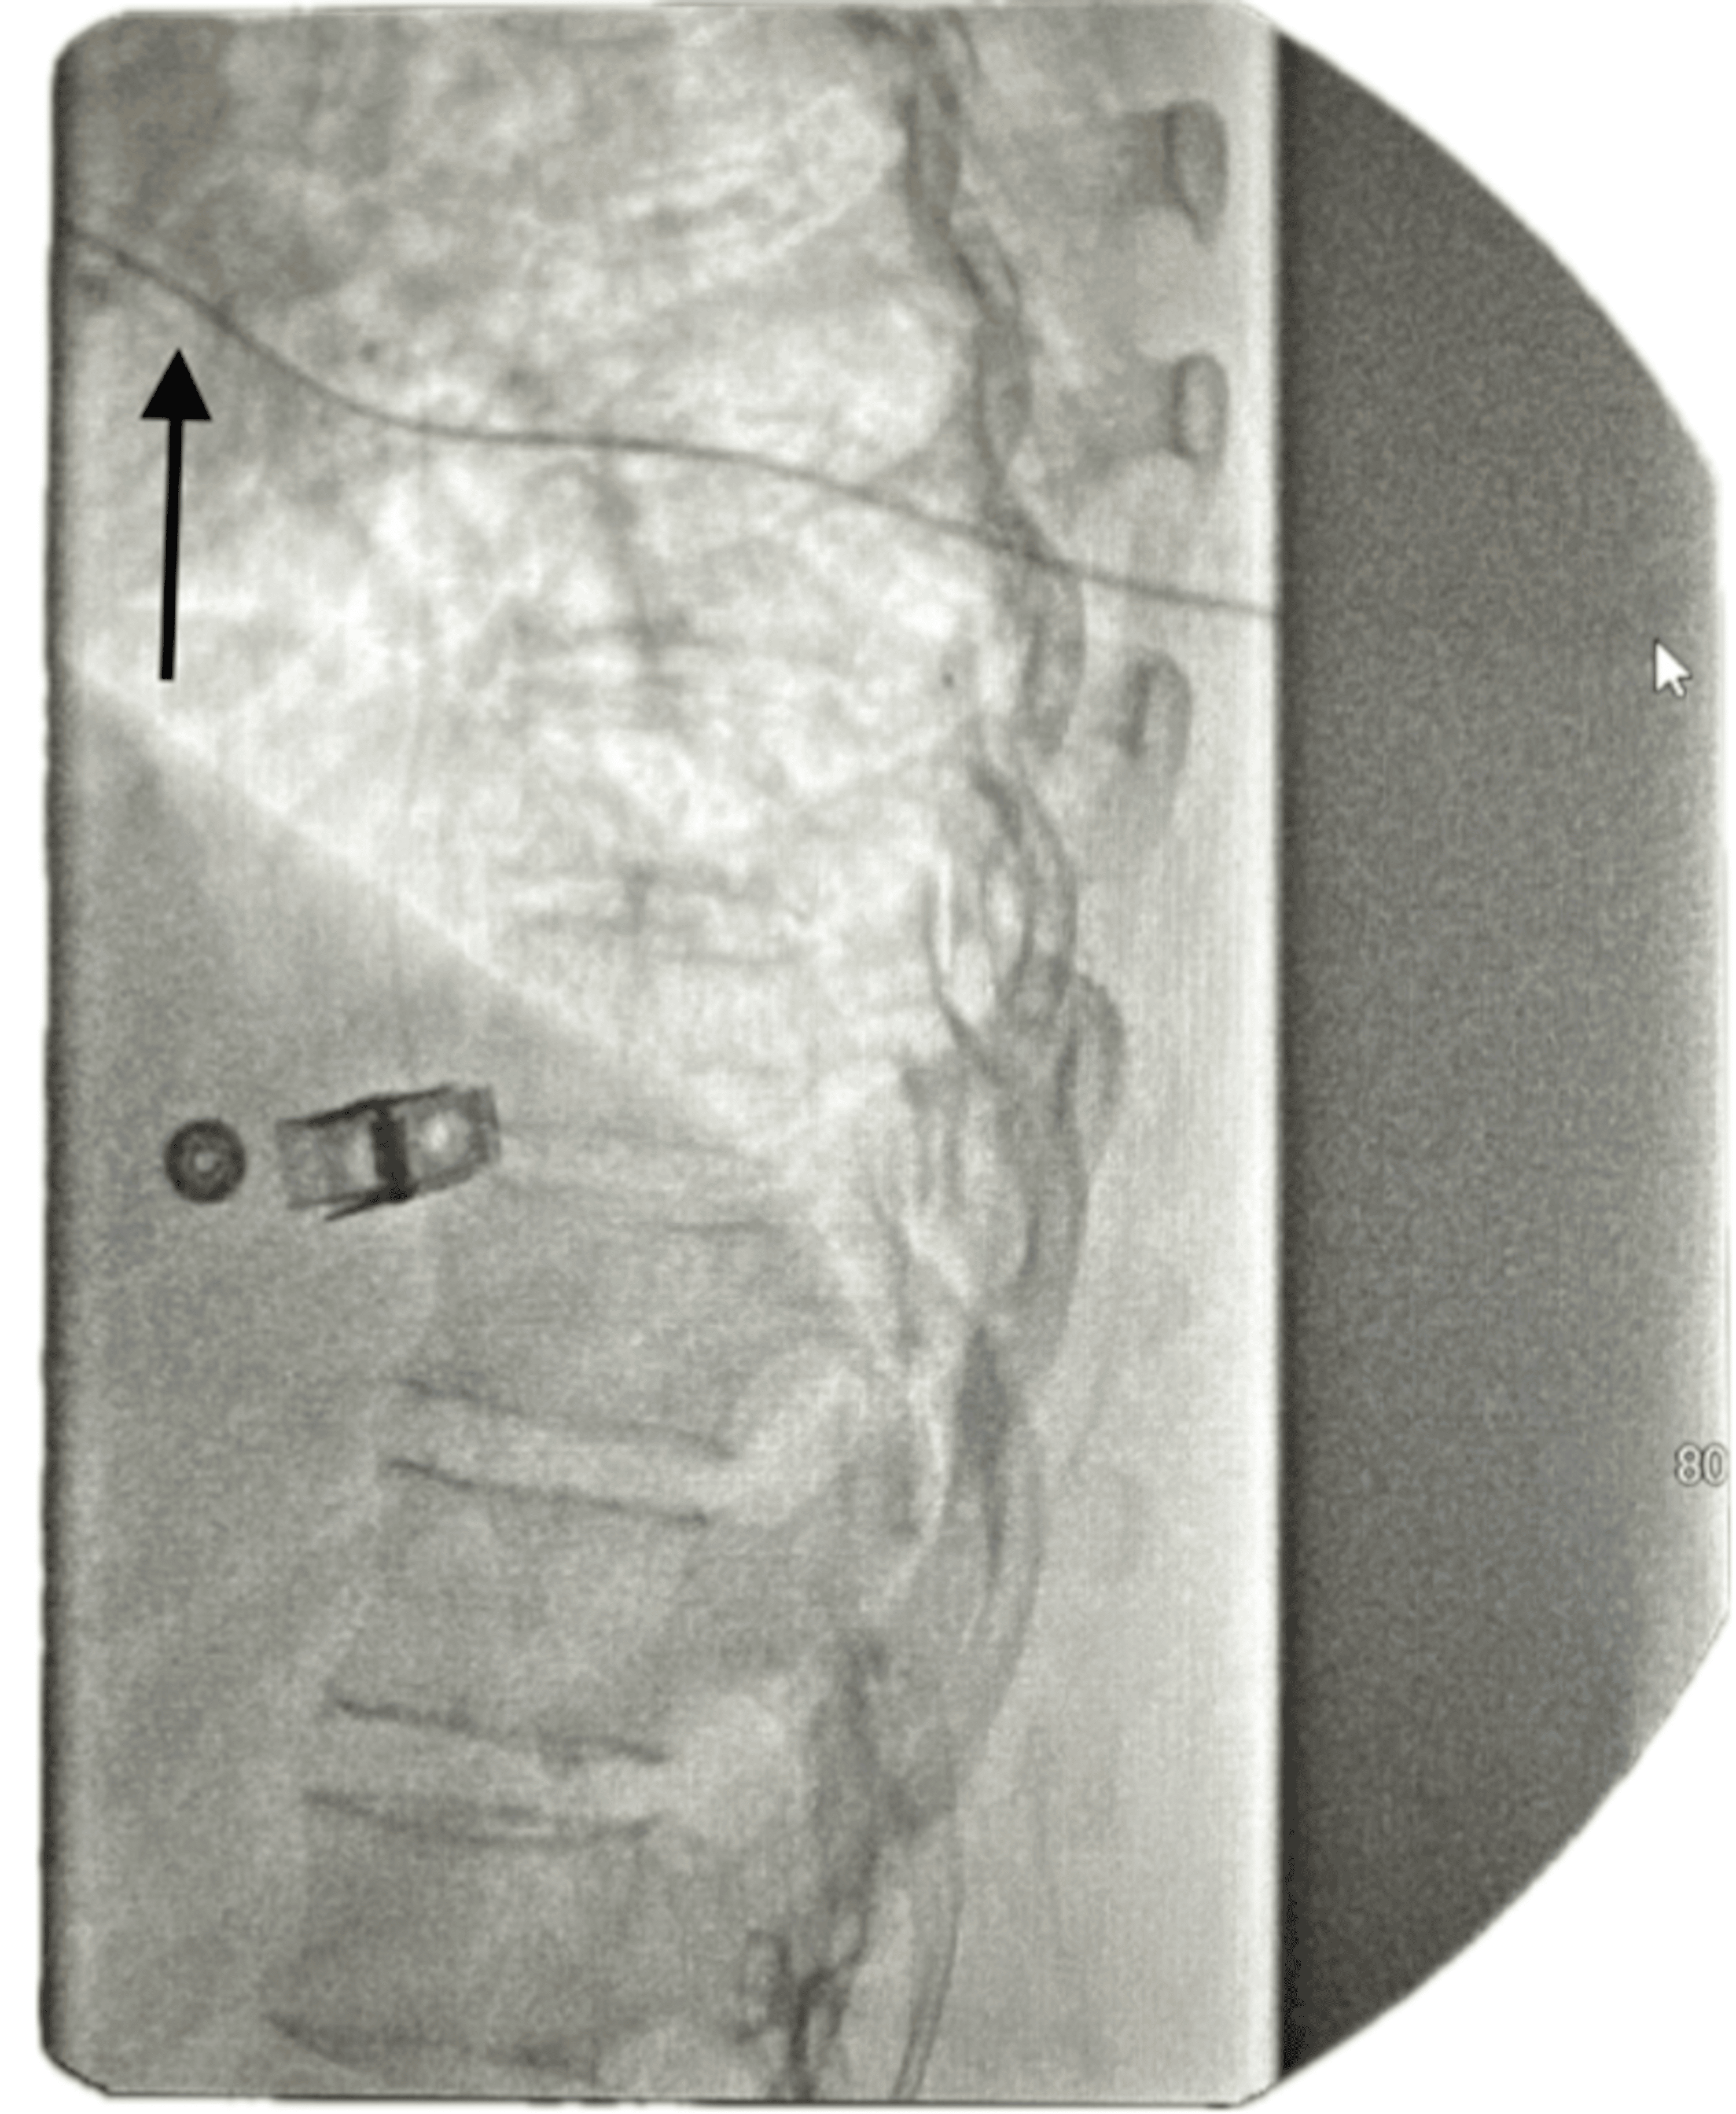

The ITP is programmed to deliver a micro-dose regimen consisting of morphine 2 mg and bupivacaine 2 mg (0.5%) in a total volume of 20 mL. The infusion rate is set at 0.7496 mg/day. The catheter tip is positioned at the T8 level within the intrathecal space, as confirmed by imaging (Figure 1). The low reservoir alarm is set to trigger at 2.0 mL to ensure timely refilling and management.